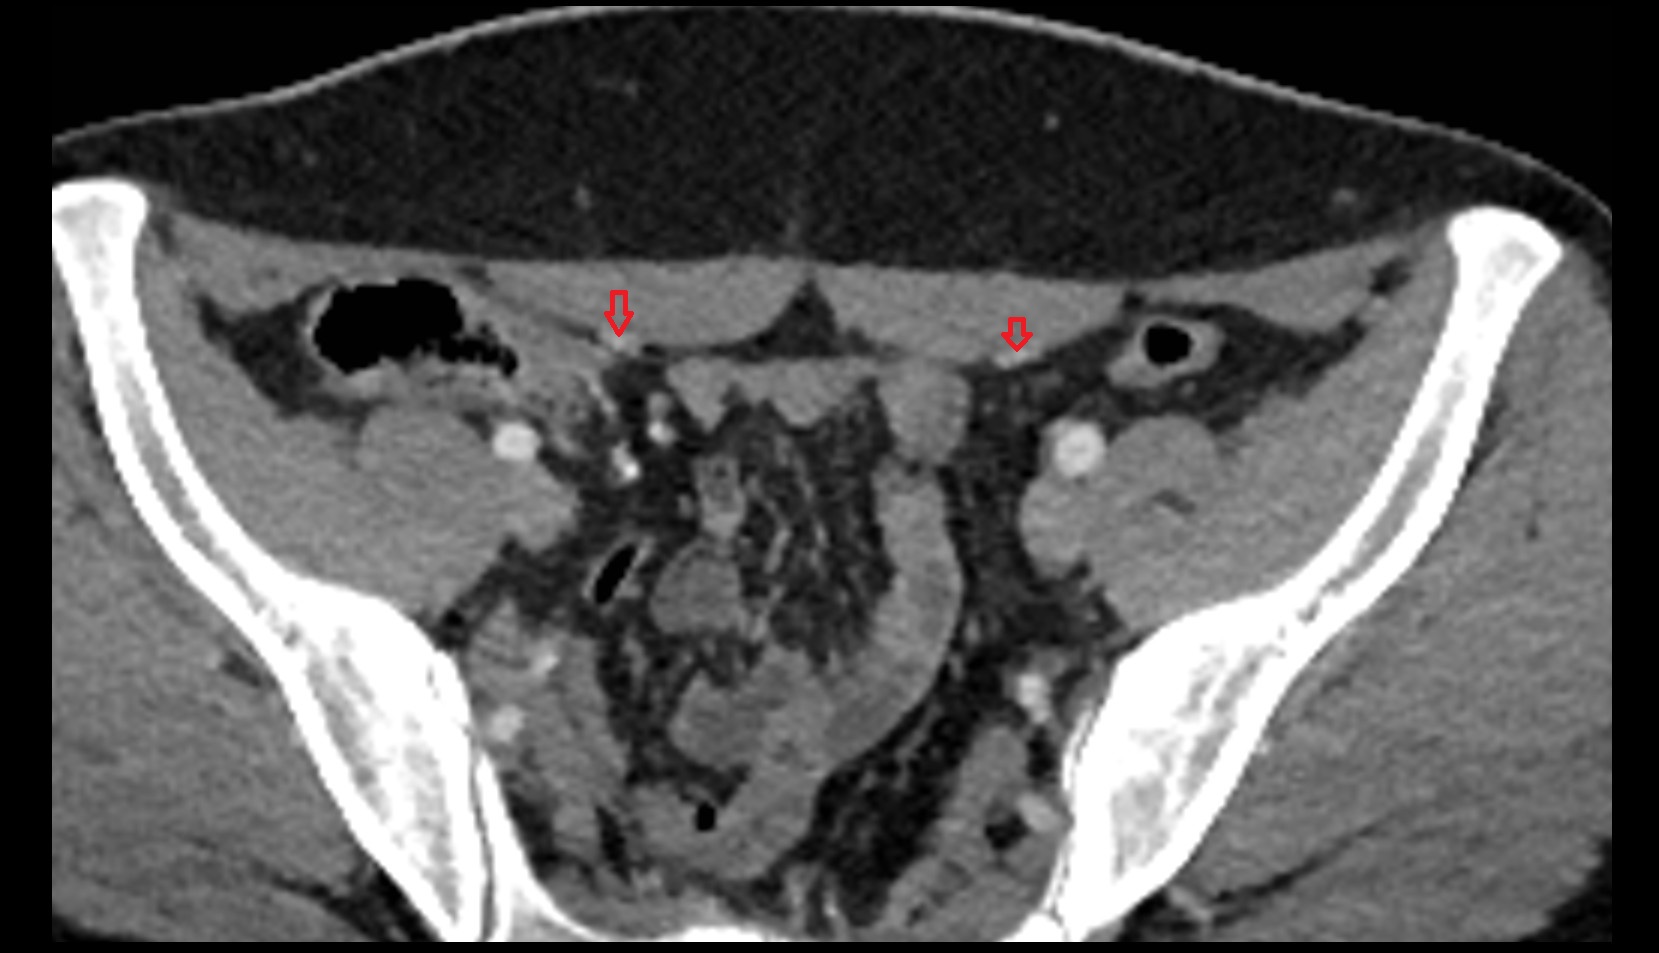

- External iliac artery

- Internal iliac artery

- External iliac vein

- Internal iliac vein

- common iliac artery